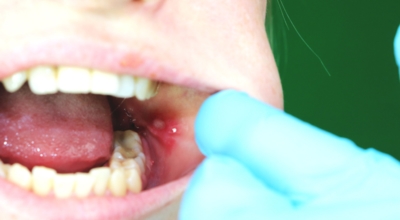

구내염 원인 - 아프타성 구내염

입안 점막이 동그랗게 패여 통증을 유발한다면, 아프타성 구내염을 의심할 수 있어요. 음식을 먹을 때마다 아픈 작은 궤양이 생겼다면, 아프타성 구내염을 의심할 수 있어요. 아프타성 구내염은 빨간색 둘레를 가진 둥근 형태의 흰색 궤양이, 얕은 깊이로 한 개 및 여러 개 생기며 통증을 동반하는 것이 특징입니다. 전 인구의 20~40%가 발병할만큼 통상적으로 나타나는 질환으로 20대, 주로 여성분들에게 많이 나타나며, 일주일 정도면 자연적으로 치유되지만 1~3개월 간격으로 빈번히 재발하는 것이 특징입니다.

까닭은 입 속 점막의 작은 상처나, 바이러스, 세균의 감염, 각별히 수면 부족이나 과로, 스트레스가 축적돼 면역력이 떨어졌을 때와, 비타민 B12 또는 엽산 결핍 시에 많이 생기 다고 알려져 있어요. 흔한 질환이니만큼 자연적으로 치유 되지만, 통증을 동반하고, 궤양의 크기가 커지거나 숫자가 늘어나기도 하기 때문에 연고나 외용제, 가글액 등을 활용해서 증상을 경감시키는 치료를 하기도 해요.